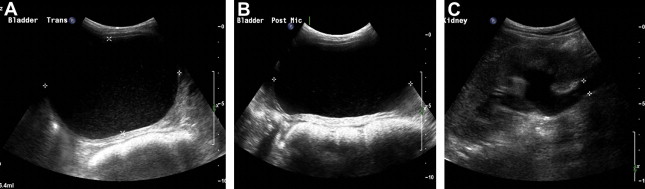

Severe constipation in patients with severe generalized recessive DEB may also result in urinary outflow obstruction with hydroureter and hydronephrosis ( Figs. 2 and 3 ), which may resolve on adequate treatment of the constipation (J.E. Mellerio, personal communication, 2009).